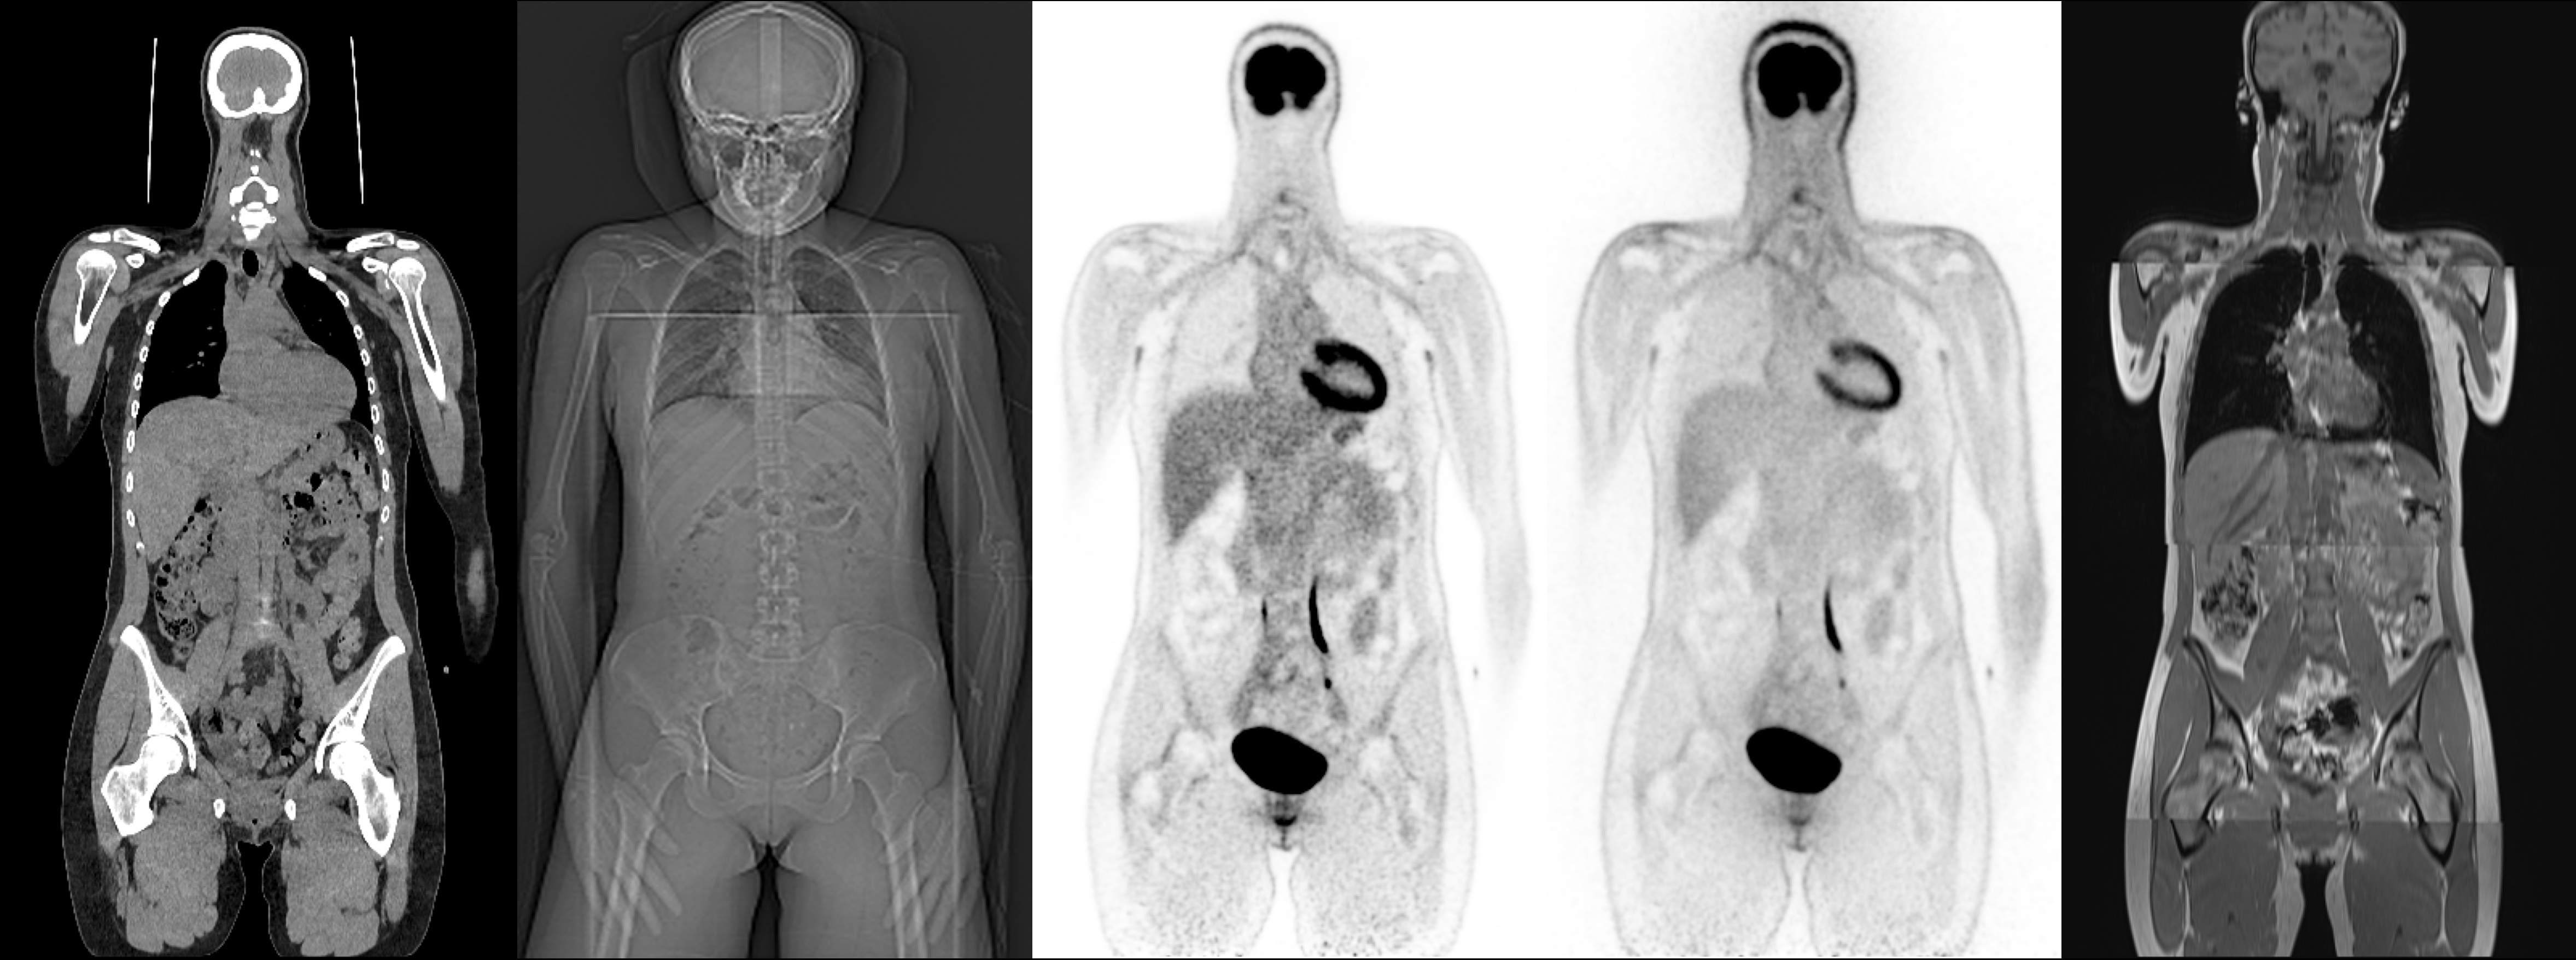

The advent of Long Axial Field-of-View (LAFOV) PET scanners has shifted the dosimetry paradigm in PET/CT

imaging. The high sensitivity of these systems allows for substantial reductions in radiotracer activity, rendering

the volumetric CT component the dominant source of ionizing radiation. For dose-sensitive populations such as

pediatric and obstetric cohorts, eliminating the volumetric CT entirely is highly desirable. However, the CT serves

a dual purpose: providing anatomical context and enabling attenuation correction (AC) for PET reconstruction,

as the attenuation map is typically derived directly from the CT. Similarly, whole-body studies acquired on

PET/MRI systems require estimation of the attenuation map from MR images. In both scenarios, the absence of

a CT poses a reconstruction challenge.

To address this, the Big Cross-Modal Attenuation Correction (BIC-MAC) challenge tasks participants with

synthesizing a 3D pseudo-CT from other available modalities. We present a novel multimodal dataset comprising

whole-body PET, CT, Topogram (scout radiograph), and MRI for 99 healthy volunteers. The cohort is age- and

sex-stratified, with data acquired on Siemens Biograph Vision Quadra and Siemens MAGNETOM Vida

scanners. Participants will receive a training set of 75 cases containing Non-Attenuation Corrected (NAC)

[18F]FDG PET images, scan-planning Topograms, and same-day DIXON MRI, alongside reference CT and CT-based attenuation-corrected PET (CTAC-PET) images. Critically, we also provide scatter maps, sinograms, and

Docker containers with open-source reconstruction software, enabling closed-loop optimization on the training

set - a capability previously restricted to hospital sites with access to proprietary vendor software.